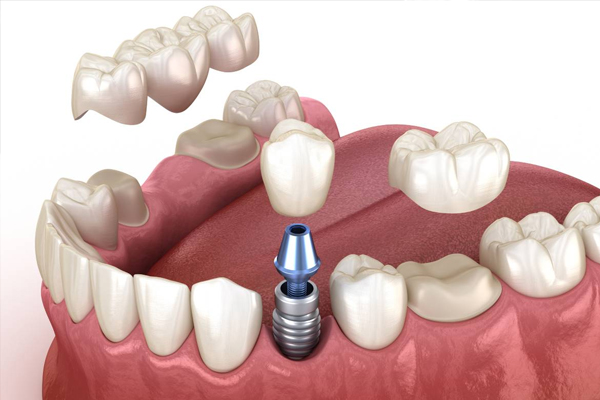

Dental implants are permanent replacements for missing teeth, secured in the jawbone. They provide a strong foundation for artificial teeth, matching the look and feel of natural teeth. Implants restore full functionality, making eating and speaking easier.

Crowns and bridges restore damaged or missing teeth, enhancing functionality. Crowns cover and protect weak teeth, while bridges replace missing ones. These treatments help maintain tooth alignment and restore natural appearance.